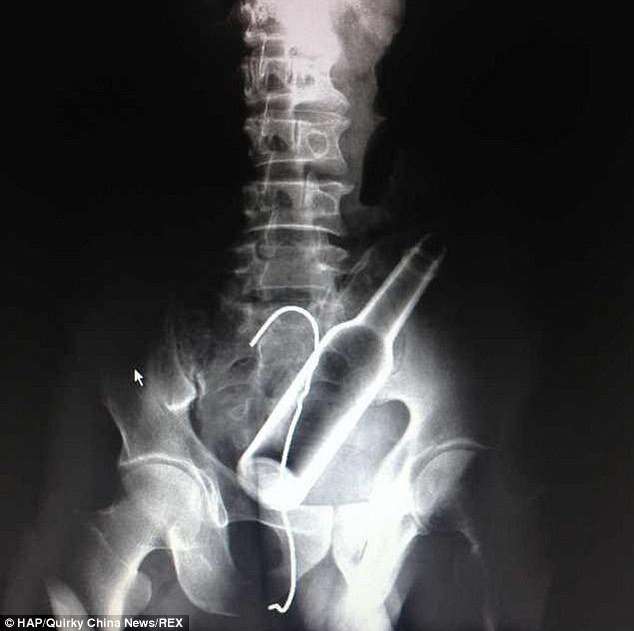

Բժիշկները, ռենտգեն հետազոտություն են արել և ցնցվել են՝ լուսանկարներում տղամարդու աղիքներում շիշ և մետաղալար հայտնաբերելով:

Այդ ժամանակ տղամարդը խոստովանել է, որ շիշը ինքնուրույն է տեղադրել հետանցքի մեջ, սակայն հետագայում չի կարողացել այն դուրս բերել: Սարսափահար եղած նա հիշել է ձկնորսական հմտությունների մասին և փորձել մետաղալարով դուրս հանել շիշը:

Նրա գործողությունների արդյունքում աղքիներում շշի հետ միասին հայտնվել է նաև մետաղալարը: Վիրաբույժների ջանքերի շնորհիվ առարկաները տղամարդու մարմնից դուրս են բերվել: Սակայն դրանով խնդիրները չեն ավարտվել, քանի որ շիշն ու մետաղալարը վնասել են նրա աղիքները, և այժմ նա պետք է բուժման երկարատև կուրս անցնի: